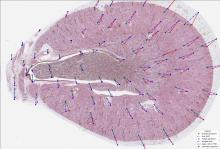

need a thumbnail